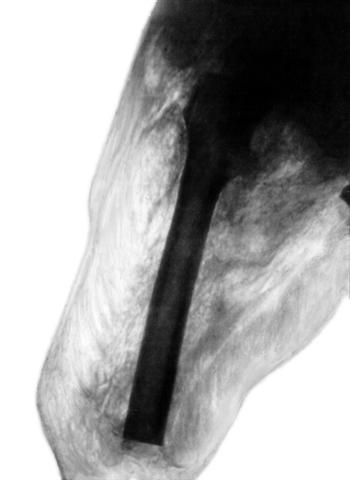

Рис. 4. Рентгенограмма культи бедра при клостридиальной инфекции: обширная газовая фрагментация практически нежизнеспособных мышц.